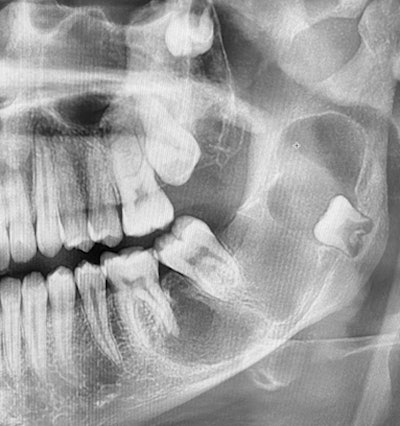

18-year-old-woman with an unusually shaped tooth

An 18-year-old asymptomatic woman presented to the dentist for a new patient exam. The patient reported no complaints. Her past medical history included chronic upper respiratory infections and type 1 diabetes. As part of the recall exam, the dentist ordered a panoramic film and noticed an unusual appearance with tooth #32.